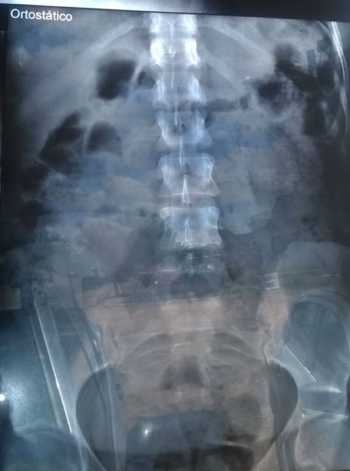

Segundo informações apuradas por nossa reportagem, Tainara Alves Pereira e Edilene Queiroz Barbosa, foram visitar companheiros que estão presos no complexo penitenciário e durante a revista de rotina, uma agente da Umanizzare desconfiou da atitude suspeita delas, que foram conduzidas para a Unidade de Pronto Atendimento (UPA) do setor Araguaína Sul e submetidas a exames de Raio X que detectaram drogas dentro das partes íntimas das duas mulheres.